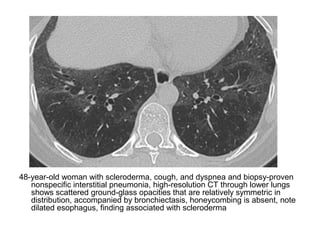

LIP in a 47-year-old woman, high-resolution CT image shows diffuse

ground-glass opacity (arrow) with multiple perivascular cysts

(arrowheads) and reticular abnormalities (*)